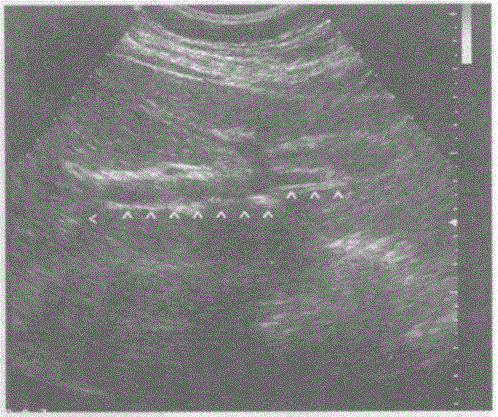

问题 下图是肝脏横切正常超声图像,请回答箭头所指部位的解剖名称:

选项 A.门静脉主干 B.第二肝门 C.第一肝门 D.肝静脉

答案 C